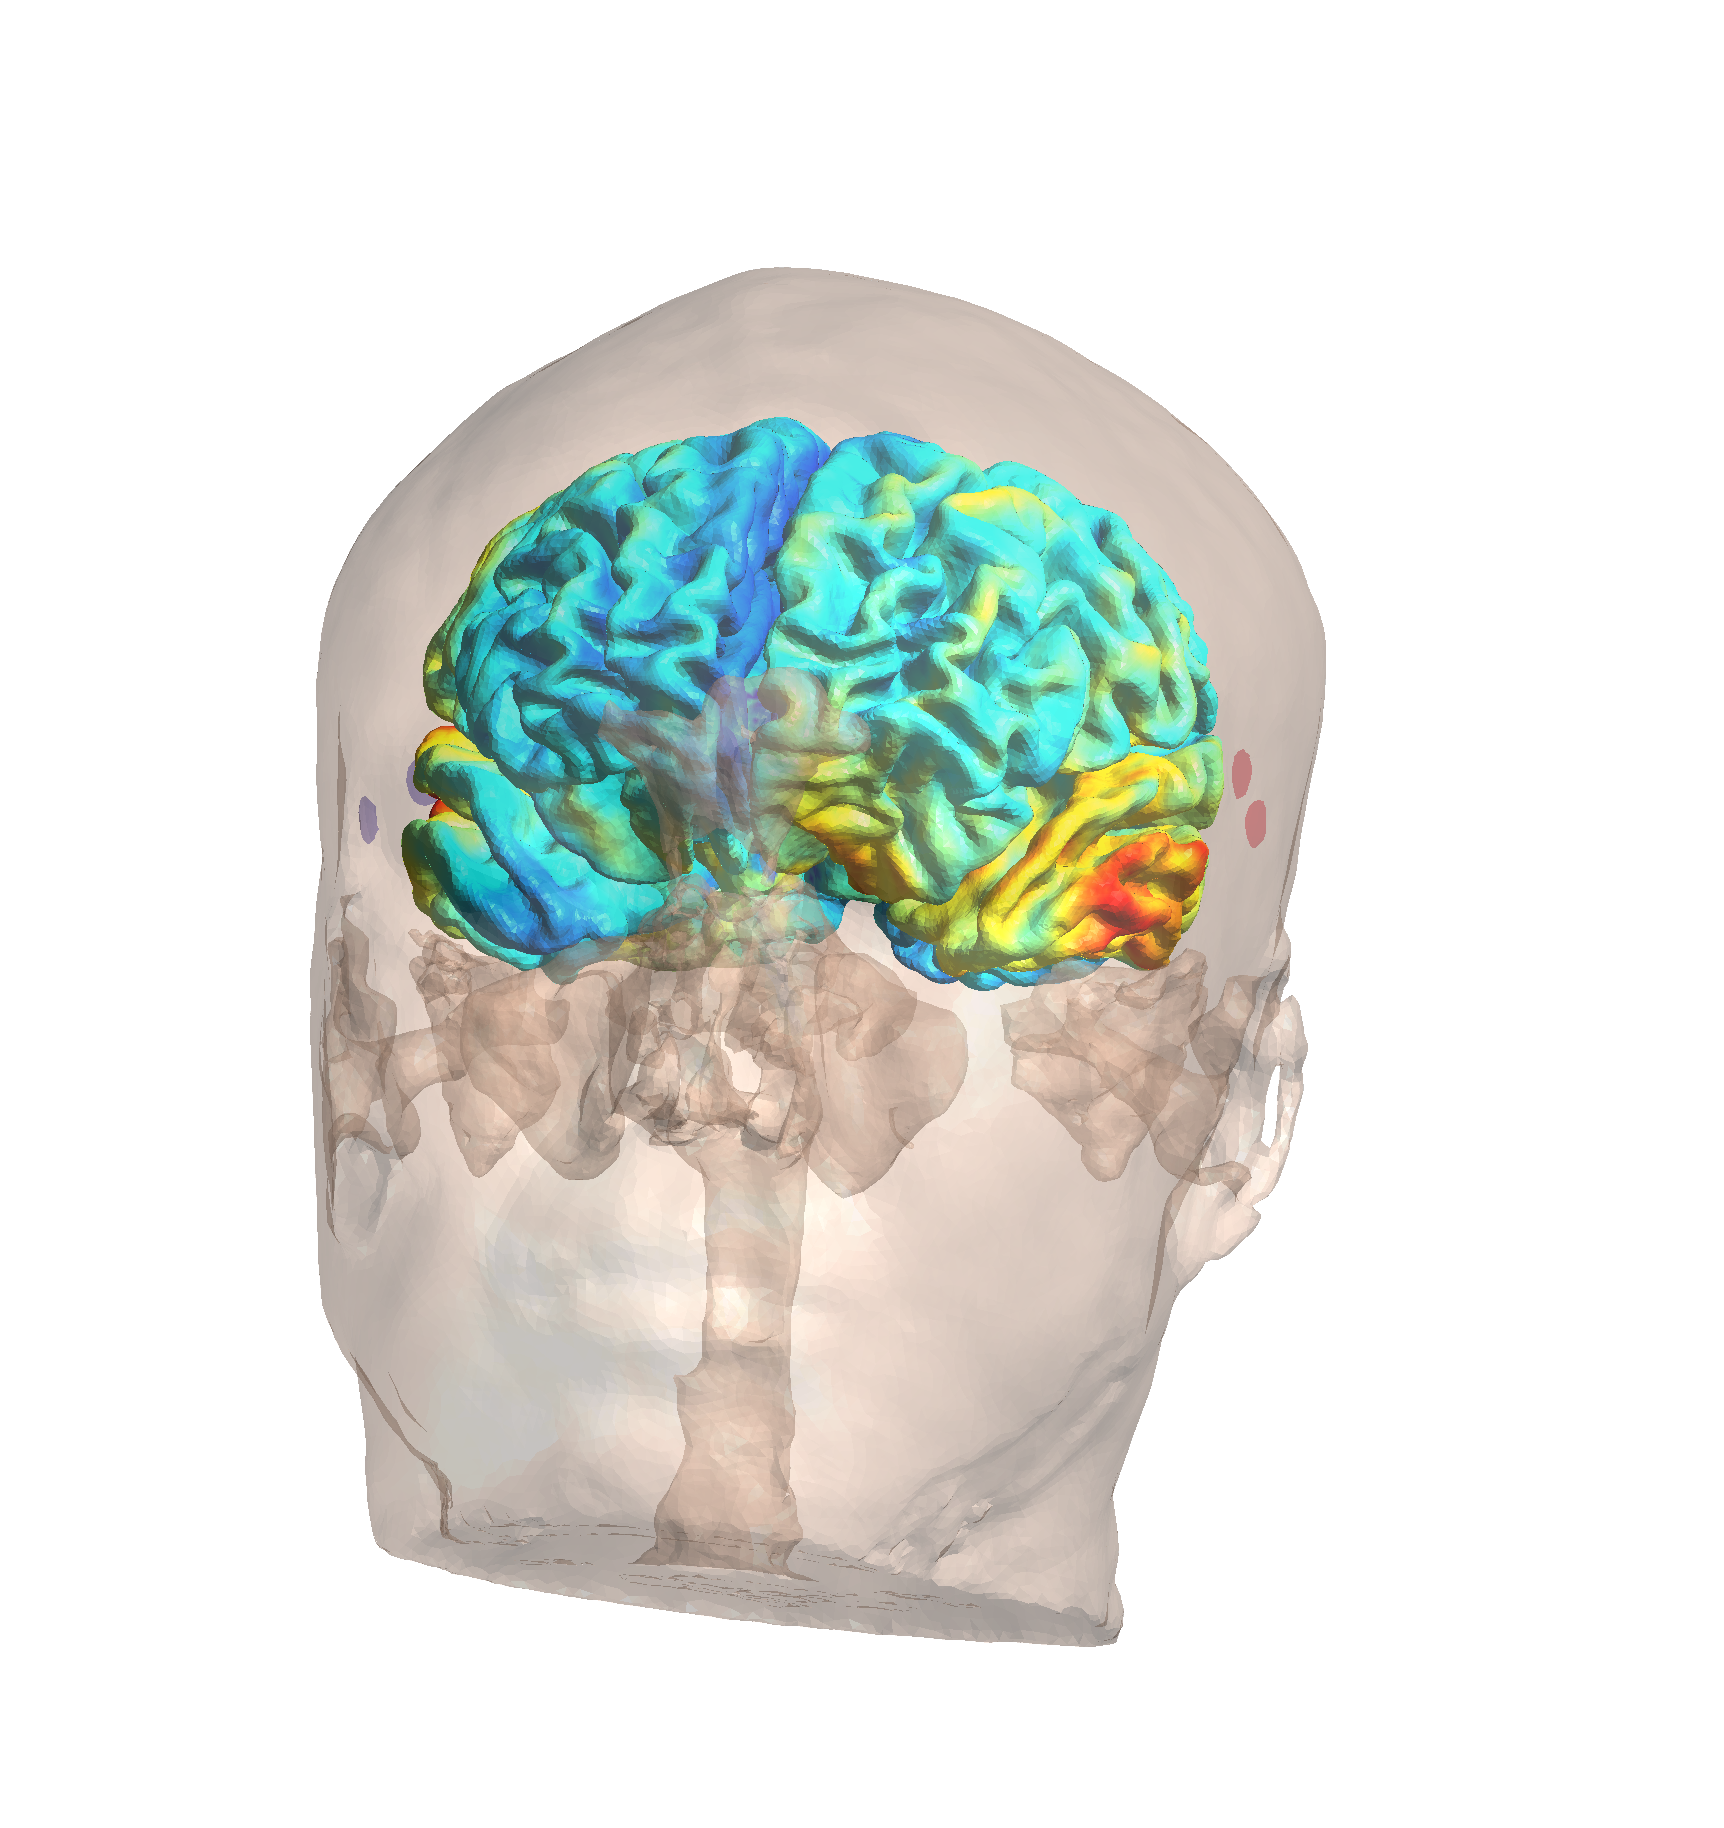

Results: Maximum TI Field Optimization

Maximum TI field distribution showing optimization results

Maximum TI field distribution showing optimization results

Optimization Summary:

| Metric | Value |

|---|---|

| Final Goal Value | -2.320 |

| Duration | 25.1 minutes |

| Peak Field (99.9%) | 4.17 V/m |

| Median ROI Field | 2.21 V/m |